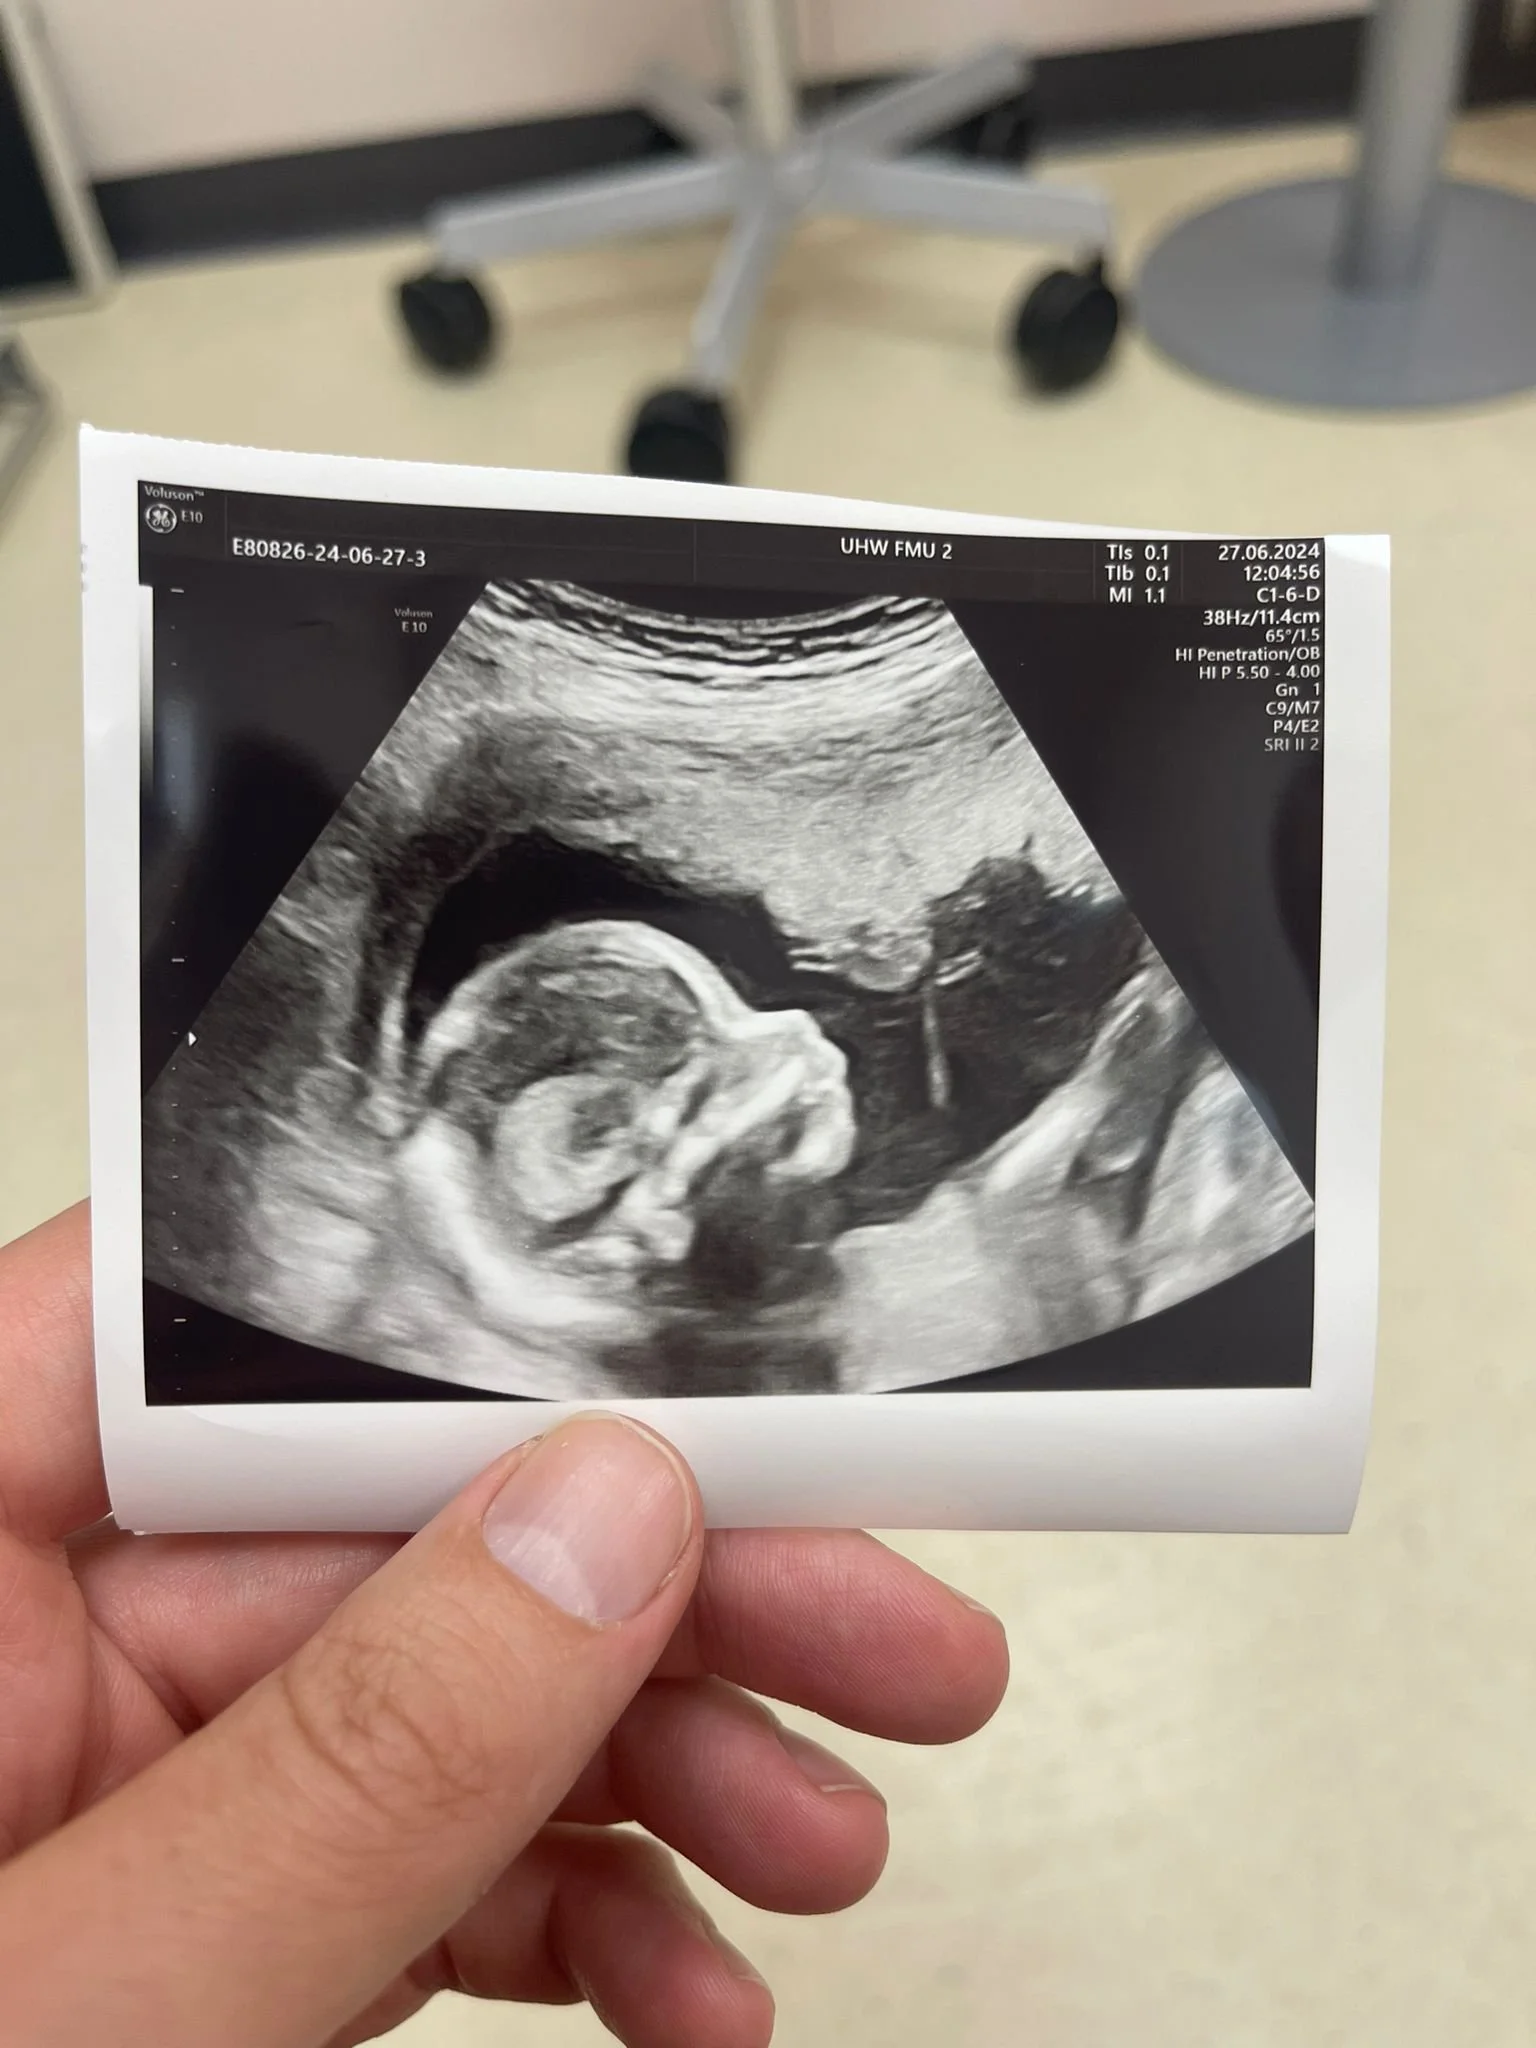

Moreover, we’ve learned that there are few things more emotionally confounding than trying to conceive again after baby loss. Imagine then, how we felt back in February this year, when we learned we were pregnant again. While overcome with joy, we were riddled with anxiety too. Despite every growth scan showing a clean bill of health and no foetal abnormalities - such as those which had previously befallen Innes - we still had lingering fears.

On Wednesday 13 November, at 7:39pm, my daughter, Nerys, entered the world alive and well. Everything went swimmingly - quite literally, as she was delivered in a birth pool, with Kim supported beautifully by a team of Community Midwives around her.

Watching Nerys rise to the surface and seeing her eyes open to greet us lovingly, my eyes swelled with tears of joy. The euphoria washed over me, leaving me feeling elated and intoxicated by a form of happiness which I thought I’d never experience again, after losing Innes. With my daughter’s arrival, I feel I have finally found my elusive missing piece.